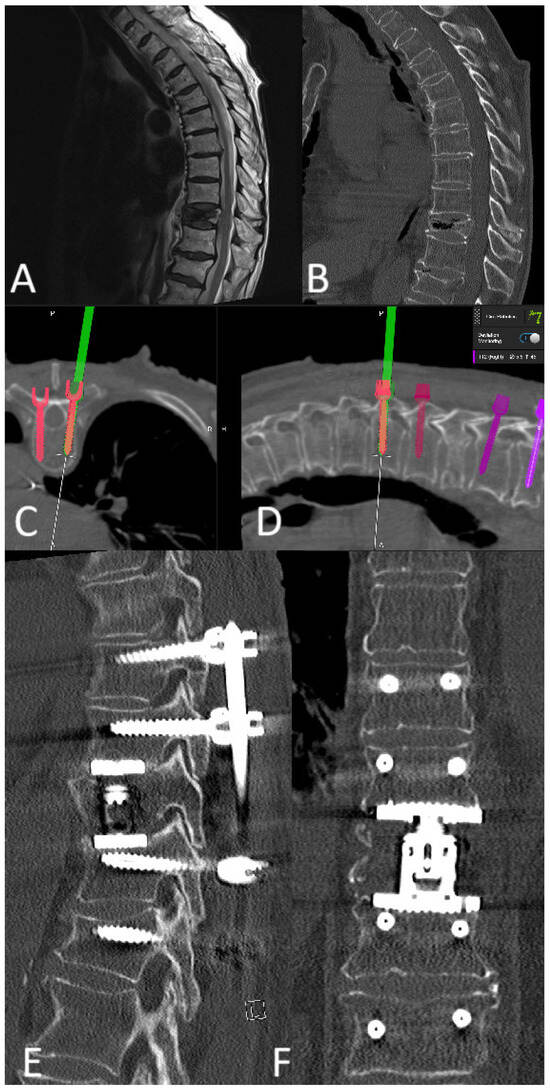

A 76-year-old patient with instability of the lumbar spine and a facet joint cyst at L3/4, following previous decompression at L2/3 on the right and L4/5 on the left, underwent RG PS implantation at L2–L5 with cage implantation (Figure 20).

3.10.2. Case 2

A 78-year-old patient with a pathological fracture of Th10 due to breast cancer metastasis underwent multi-stage surgery: RG PS placement at Th8/9-L1/2, followed by implantation of an expandable vertebral body cage via a left transthoracic approach. All screws were GRS A (Figure 21).

3.10.3. Case 3

An 81-year-old patient with spondylodiscitis, intraspinal empyema at L2-S1, and an L4 fracture underwent decompression for empyema evacuation and RG PS placement at L2-S1, followed by cage implantation (Figure 22, Figure 23 and Figure 24).

3.10.4. Screw Revision Case

A 63-year-old female patient with Th9 metastasis of renal cell carcinoma underwent Th7/8-10/11 RG stabilization with decompression of the spinal canal and partial resection of the tumor. The reference array was placed proximally to the surgical field and fixed to the spinous process of Th7. K-wires were inserted in a proximal-to-distal sequence, and screws were placed in a distal-to-proximal sequence. The distal screws (Th10/11) were GRS A screws, while the last screw (left Th7 screw) was a GRS E screw due to possible unintended movement of the reference array, which led to major navigation inaccuracy and further screw skiving. Fortunately, no major vessels or pulmonary injuries occurred. The screw was removed, and a new screw was inserted, this time a GRS A screw. (Figure 25).